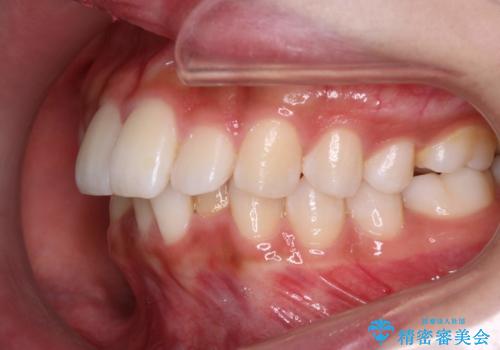

Invisalign インビザラインによる軽度なガタつきの改善

- 奥歯の位置関係はそこまで大きくいじらず、前歯群のみでガタつきの改善を計画しました

奥歯の位置関係に改善の余地はありますが、機能的に問題のない cusp to fossa の関係で咬めているため、前歯のガタつきを前歯のみで改善するというシンプルな計画で、短期間で治療を終了させました。